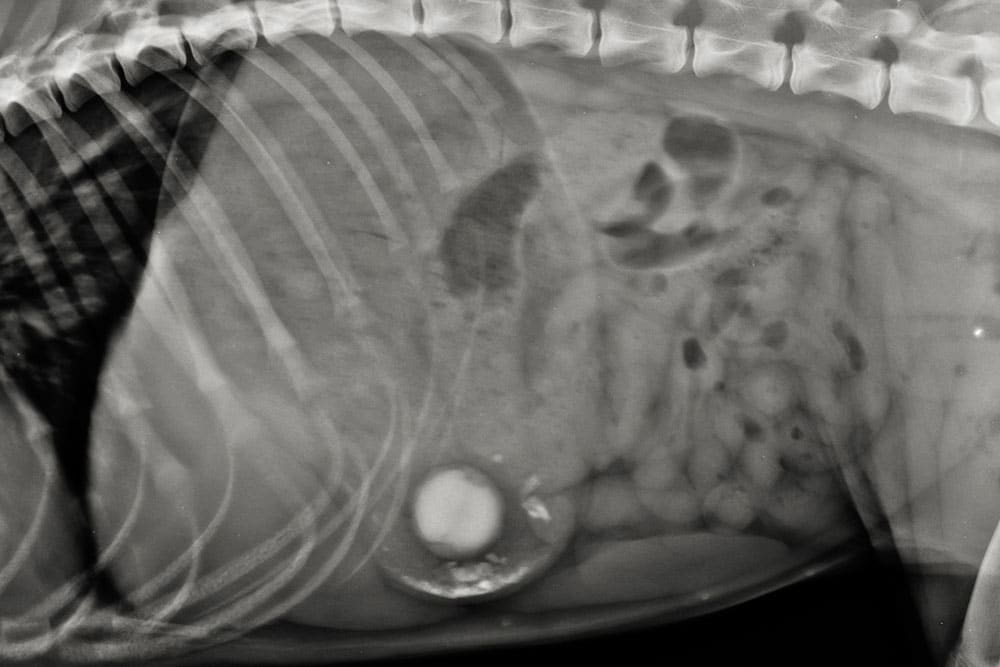

X-ray image showing the side view of an animal’s torso, possibly a dog, with visible spine, ribs, and internal organs. A round, dense object is visible in the abdominal area, possibly indicating a foreign object.

Once a pet arrives, our veterinary team begins with a physical exam and stabilization. Palpating the abdomen often reveals pain or tension, while vomiting or bloating help confirm suspicion. We use advanced digital X-rays to locate objects and assess intestinal function.

Our on-site diagnostics allow for rapid results, helping determine whether surgery is required or if noninvasive approaches are possible. In complex cases, we may perform contrast studies to track object movement through the gastrointestinal tract or identify partial obstructions that could otherwise go unnoticed.